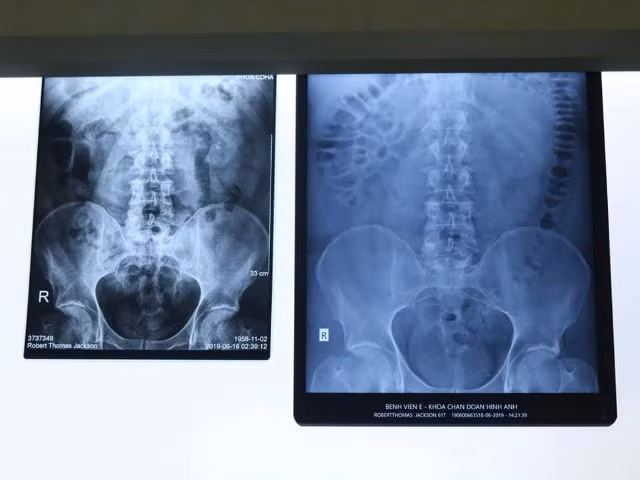

Bệnh nhân ngay lập tức được làm xét nghiệm, chụp X-quang, kết quả cho thấy, bệnh nhân bị sỏi niệu quản ở vị trí 1/3 trên, bên phải.

| Hình ảnh viên sỏi trong niệu quản. |